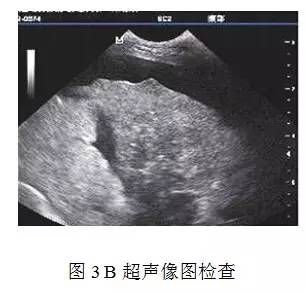

2.3.2 B超检查

结果见图3,由该图可以看出肝区回声增强,即肝区光点增多,变粗或有小光团,而且光点分布不均匀,表明肝部有病变。

B 型超声波检查可见肝脏表面粗糙,肝被膜增厚以及肝实质回声增强且粗糙不匀称,肝脏门静脉直径增宽,脾大,不等量腹水,可作为肝硬化的辅助诊断方法。